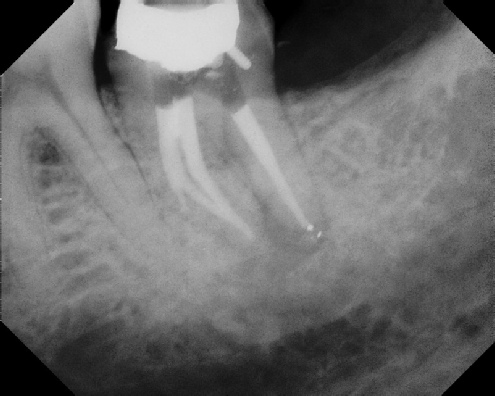

COMPLICATED ANATOMY LARGE LESIONS CALCIFIED CANALS PERFORATION / RESORPTION SEPARATED INSTRUMENTS SURGICAL CASES RETREATMENT / pOST REMOVAL OPEN APICES ACCESS THRU CROWNS Root Canal Case Portfolio